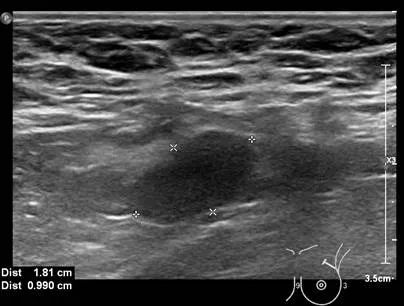

女性,32岁,来院行乳腺超声检查,超声所见如图

解读:该女性左乳下方(6点)可见一约0.6cm大小的低回声结节,界清,形态规则,未见明显血流信号。根据超声所见良性结节考虑,定期随访即可。